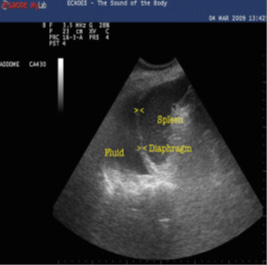

Upper left quadrant

Fluid can collect in the space between the spleen and the left kidney, the splenorenal flexure, similarly to the right side, settling between the 2 organs. Its exploration is similar to that of the right side, except for the higher and posterior location of the left kidney due to the little displacement produced by the spleen, for this reason visualization is more difficult due to the acoustic shadows produced by the ribs and requires that the evaluation be performed during the patient's inspiration, without forgetting that the transducer must be in a more posterior position (Figure 5 A and B). A complete evaluation should include the space between the spleen and the left kidney in its entirety to look for free fluid. Contrary to the evaluation of the right side, it is very common for the fluid to be located between the spleen and the diaphragm, so this area should also be examined.

Damage to the spleen can also be detected and appear similar to damage to the liver.

Fluid in the pleural cavity can also be seen in the left lung base, and will be seen as a hypoechoic area over the spleen and diaphragm.